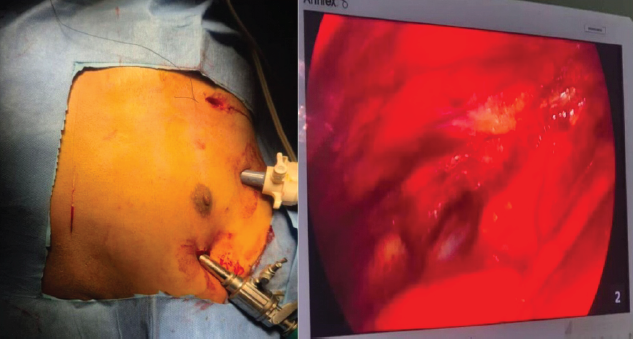

Surgery was scheduled for May 20, 2024. The patient was positioned supine on the operating table under general anesthesia, utilizing a fluoroscopy-compatible table with support beneath the shoulder blades (Fig. 2).

Figure 2: Positioning of the patient on operating table.

After the surgical site was prepared and draped, the CTVS team performed thoracoscopy through three portals to visualize the displaced fracture and any adhesions (Fig. 3).

Figure 3: Video-assisted thoracoscopy through 3 portals.

They meticulously removed the adhesions while protecting the underlying vital structures (Vid). A 6–-8 cm straight incision was made over the fracture site, which was opened in layers to access the fracture. After cleaning the fracture ends, we encountered difficulty in reducing the fracture due to the inability to use forceps or retractors. Consequently, we opted to place a 3.5 mm Schanz screw in the proximal fragment and applied traction with a periosteal elevator to facilitate reduction under thoracoscopic guidance (Fig. 4).

Figure 4: Reduction of fracture by Schanz screw and periosteal elevator.